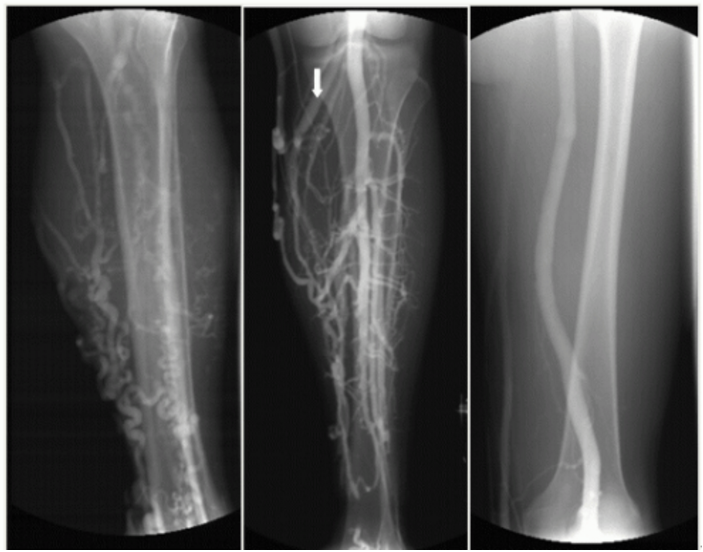

下肢靜脈曲張――微創(chuàng)介入硬化治療

下肢靜脈曲張X線造影圖像!像蚯蚓一樣在患者小腿之上縈繞!